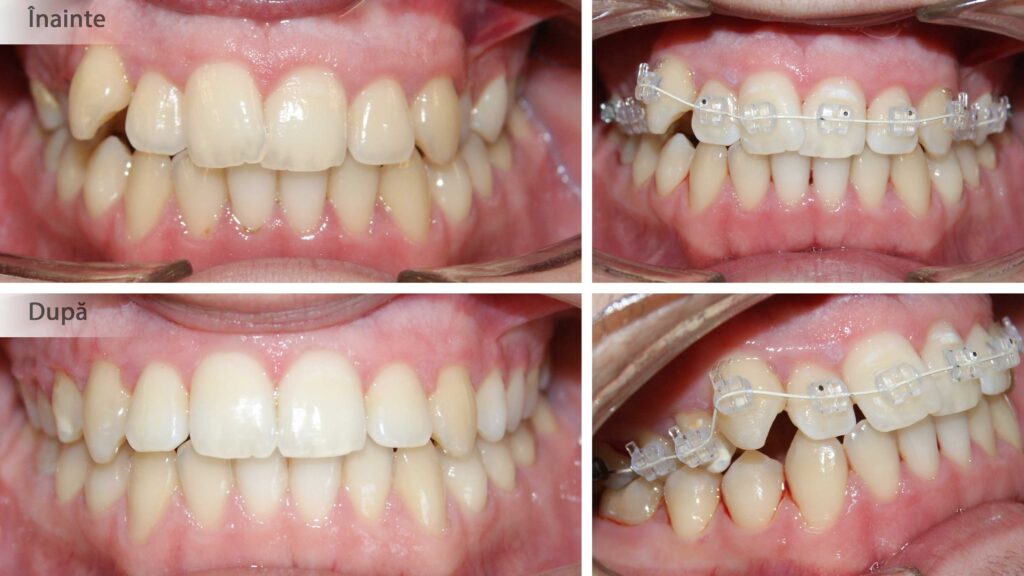

În cazul de față ortodonția ne-a ajutat să oferim lărgime semnificativă zâmbetului și să prevenim retracțiile gingivale de pe caninii inferiori prin distalizare.